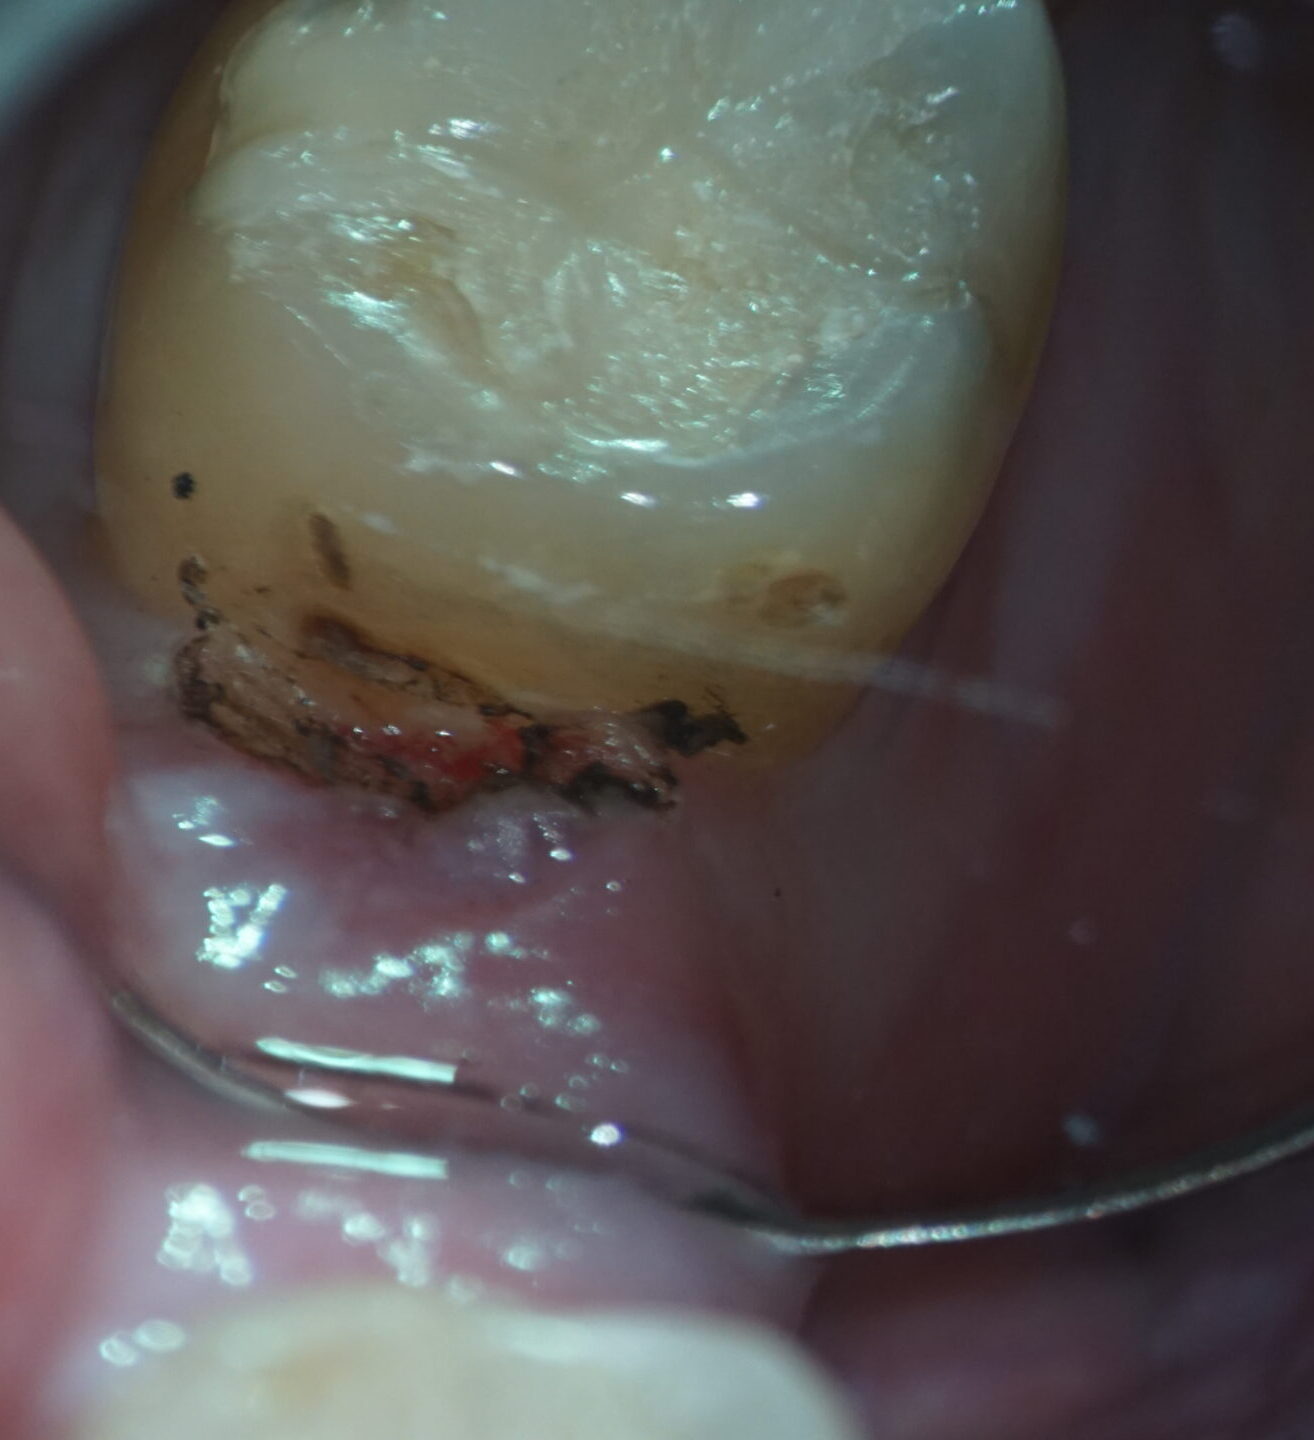

↑歯肉はレーザーで一部焦げます。出血を抑えた状態で虫歯が露出し、綺麗に虫歯除去できました。